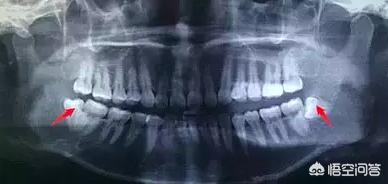

1) Si vous êtes un jeune ou un étudiant et que vous avez mal à la tête, vous devez penser à vous rendre dans le service de stomatologie d'un hôpital ou vous y rendre, et prendre un cliché dentaire pour voir s'il y a un problème.Dents obstruées, dents de sagesseRecommandations, le cas échéantretirerComme ces dents poussent anormalement ou sont trop profondes, il n'est pas facile de les brosser proprement et elles sont sujettes à des inflammations récurrentes, ce qui déclenche souvent des maux de tête. Cela affecte les études, le travail et la vie.